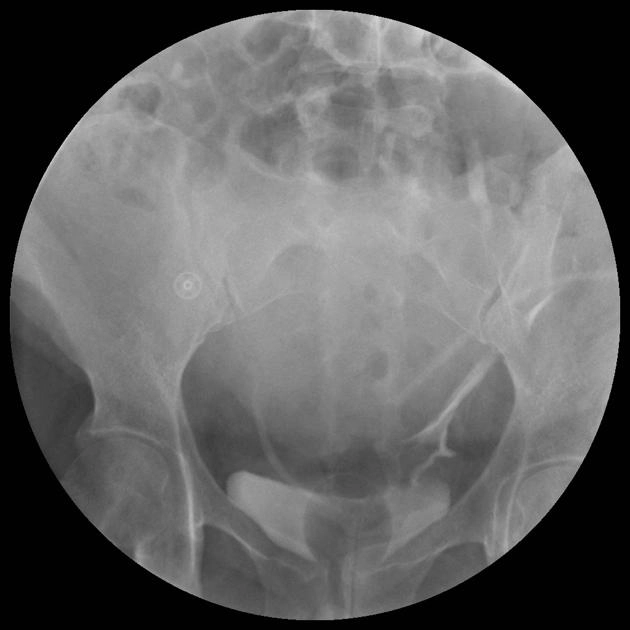

Trào ngược bàng quang-niệu quản (Vesicoureteric Reflux - VUR)